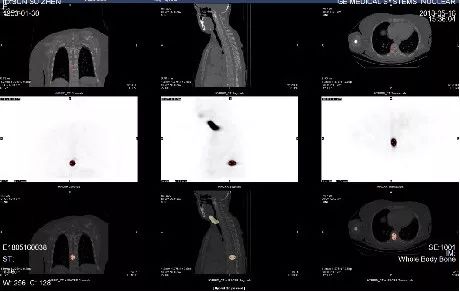

骨转移:碘-131对骨转移病灶治疗的疗效虽不如肺转移,但通过治疗可以控制病灶进展,缓解局部症状,从而提高生活质量,延长生存期。

甲状腺癌骨转移